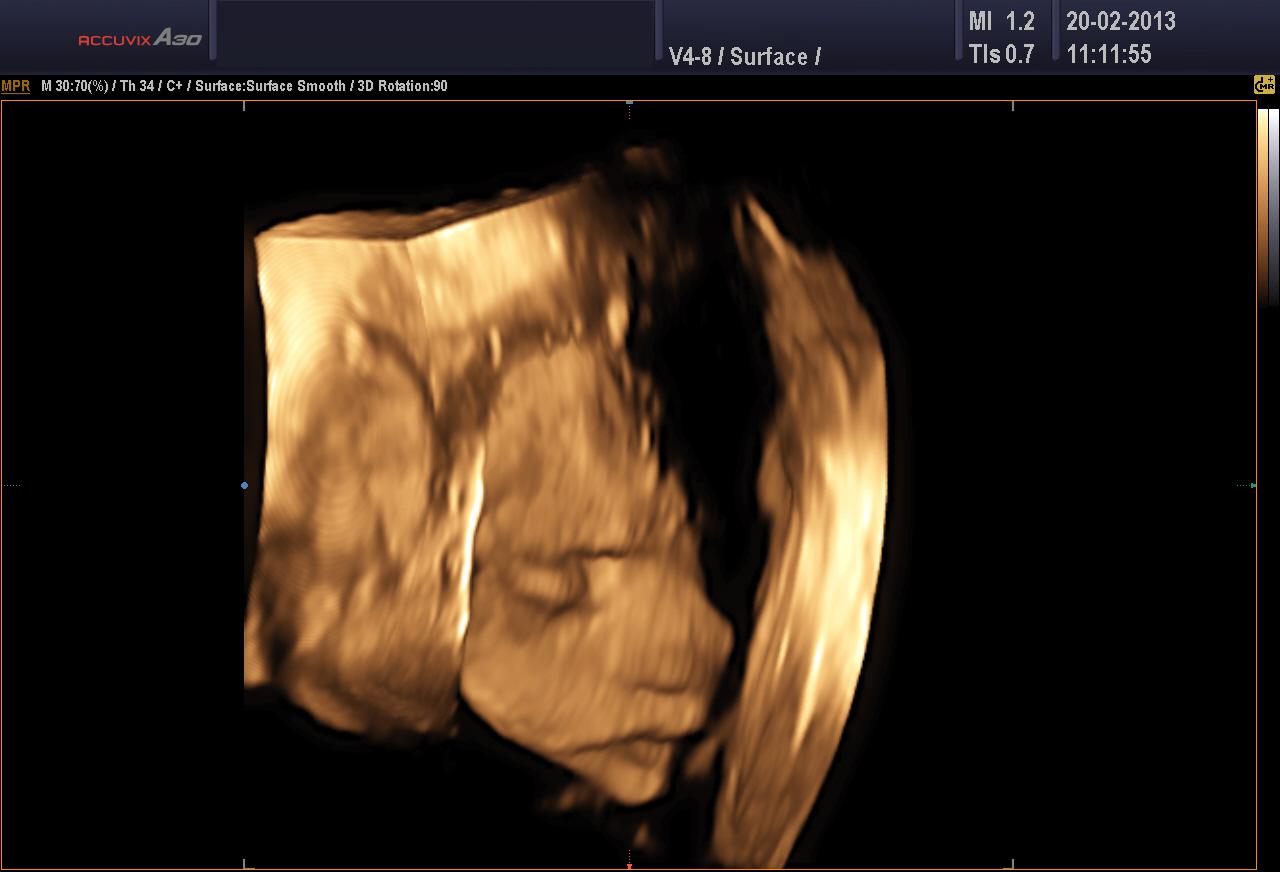

Dnes mam za sebou hruznou noc,nastesti s dobrym koncem.Ve 23hod jsem zacala hodne krvacet,asi za 15min ze me odesel asi 5cm hematom,pak krvaceni preslo a jen jsem spinila.Volala jsem do car,ale protoze to mam 40km doporucili lezet a prijet rano.Dnes jsem 6+5 a ultrazvuk je v poradku a tukaji nam obe srdicka 😵 .Jsem strasne stastna.Musim lezet a zas zobat ascorutin.Snad uz bude vse ok.Dalsi ko mam 1.3.

Kerky drž se!!! Taky nás trápil hematom,hodně se to stává. Pěkně odpočívej, to je super, že vám tlučou obě srdíčka 🙂 .